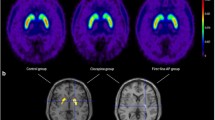

Quinpirole dose-dependently lowered DA levels in MPFC as well as in the striatum. NAA(−) alone transiently lowered DA levels (80 % baseline) in the striatum, but had no effect in MPFC. The co-administration of NAA(−) and a subthreshold concentration of quinpirole (6.25 nM) lowered DA levels (50 % baseline) in both the MPFC and striatum. This effect was blocked by the mixed D2R/D3R antagonist haloperidol at IP doses that on their own did not affect DA levels (10.0 nmol/kg in the MPFC and 0.10 nmol/kg in the striatum).

The acute lowering of brain tyrosine (TYR) levels lowers brain DA turnover and/or efflux in the rat (Biggio et al. 1976; Fernstrom and Fernstrom 1995; Jaskiw et al. 2005; McTavish et al. 1999a; Wurtman et al. 1974) as well as in non-human primates (Palmour et al. 1998). In man, TYR depletion is generally well tolerated; its central anti-dopaminergic actions include the attenuation of manic symptoms, (McTavish et al. 2001), amphetamine antagonism (McTavish et al. 1999b), elevation of prolactin, and changes in DA-mediated indices of cognition and emotion (Gijsman et al. 2002; Harmer et al. 2001; Harrison et al. 2004). However, in vivo imaging shows that TYR depletion produces a rather modest (∼20 %) decline in extracellular DA levels in man (Montgomery et al. 2003). This may account for reports in which the lowering of TYR levels did not produce the expected effects (Ellis et al. 2007; Lythe et al. 2005; Mehta et al. 2005). The research utility of TYR depletion would be enhanced if associated changes in brain DA levels were larger and more consistent. We now report on one such strategy in the rat.

Clinical research implications

Apomorphine is a clinically available (LeWitt et al. 2009) direct DA agonist that at low doses stimulates inhibitory receptors and lowers extracellular brain regional DA levels in the rat (Adachi et al. 2000; Bean et al. 1990; Rodenhuis et al. 2000) as well as in man (de La Fuente-Fernandez et al. 2001). However, the dose of apomorphine that effectively lowers extracellular DA brain levels in man (03–0.6 mg/kg SC; de La Fuente-Fernandez et al. 2001) overlaps with the threshold (0.4–0.5 mg/kg SC) for inducing emesis (Angrist et al. 1980). Our data suggest that administering NAA(−) in combination with a dose of apomorphine subthreshold both for lowering the DA levels and inducing emesis would lower extracellular brain DA levels by about 50 % (Fig. 2). This level of DA depletion should provide a reliable and valuable probe of human brain regional DA systems without inducing extrapyramidal (Nord and Farde 2011) and other side effects.